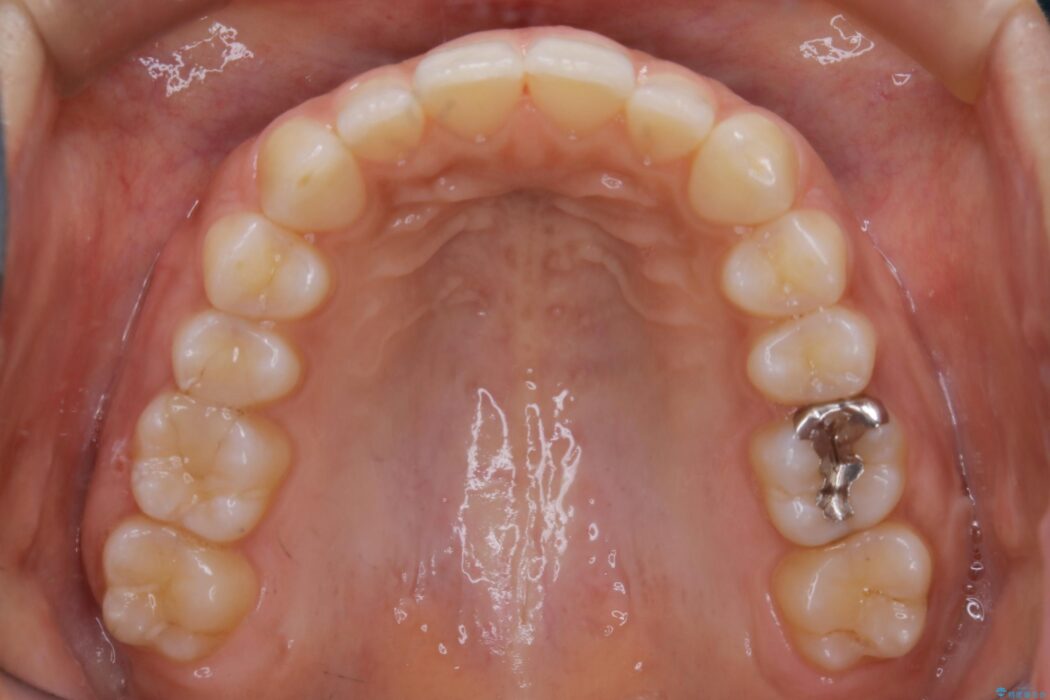

気になるガタツキと噛み合わせを改善したいとご来院されました。

下の歯列よりも上の歯列が前に出ている状態を治すため、マウスピース矯正に加え、患者様にゴムかけのご協力をいただきました。その結果、ガタつきが改善し、上下の噛み合わせが適切な位置で合うようになりました。